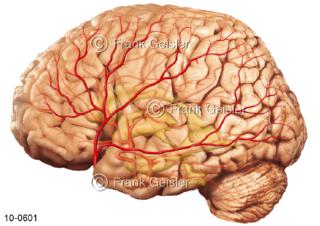

Bildergalerie Nervensystem

Bilder zum Nervensystem,dem Gehirn, Teil des zentralen Nervensystem, Zentralnervensystem ZNSmit Rückenmark, Abbildungen zum Nervengeflecht (Nervenplexus), die Verflechtungen von Nervenfasern, aus der Wirbelsäule hervortretende Nervenäst sowie Nervenzellen der Nerven